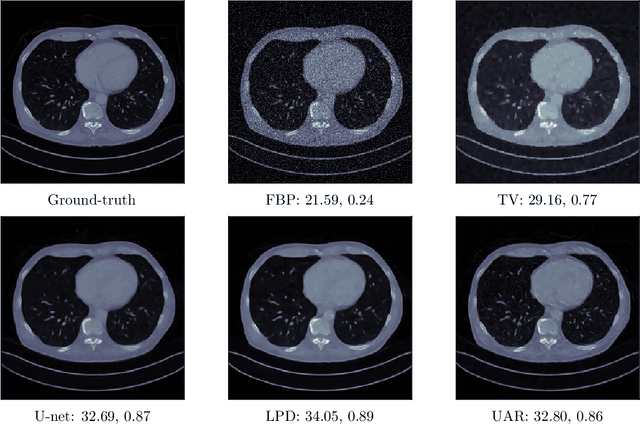

Abstract:Combining the strengths of model-based iterative algorithms and data-driven deep learning solutions, deep unrolling networks (DuNets) have become a popular tool to solve inverse imaging problems. While DuNets have been successfully applied to many linear inverse problems, nonlinear problems tend to impair the performance of the method. Inspired by momentum acceleration techniques that are often used in optimization algorithms, we propose a recurrent momentum acceleration (RMA) framework that uses a long short-term memory recurrent neural network (LSTM-RNN) to simulate the momentum acceleration process. The RMA module leverages the ability of the LSTM-RNN to learn and retain knowledge from the previous gradients. We apply RMA to two popular DuNets -- the learned proximal gradient descent (LPGD) and the learned primal-dual (LPD) methods, resulting in LPGD-RMA and LPD-RMA respectively. We provide experimental results on two nonlinear inverse problems: a nonlinear deconvolution problem, and an electrical impedance tomography problem with limited boundary measurements. In the first experiment we have observed that the improvement due to RMA largely increases with respect to the nonlinearity of the problem. The results of the second example further demonstrate that the RMA schemes can significantly improve the performance of DuNets in strongly ill-posed problems.